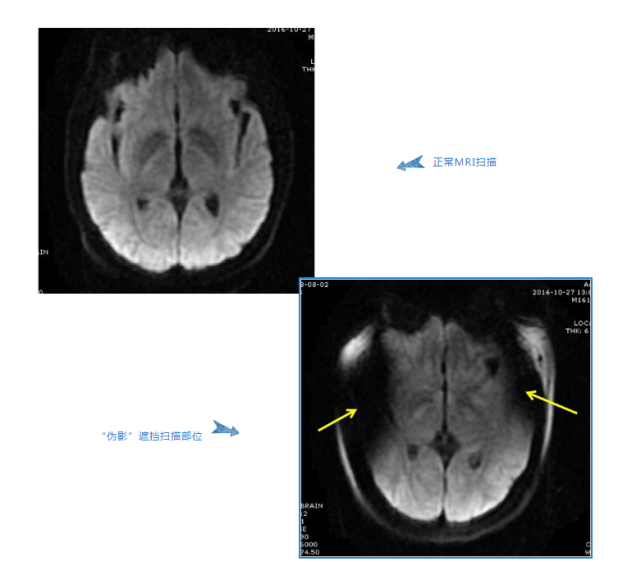

此外,染发剂、化妆品中含有的重金属盐也有可能附着在身体上。在 MRI 检查时,这些物质会对图像造成干扰,成为伪影,甚至还会干扰医生对病变的诊断。